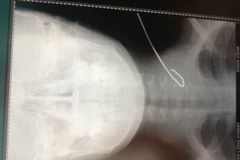

Bệnh viện đa khoa khu vực Long Khánh (Đồng Nai) đã cứu sống cháu Nguyễn Chí Công theo cha đi cắt cỏ bị cọng thép 10cm vô tình bắn lên và đâm sâu vào cổ đâm xuyên thủng tĩnh mạch cảnh.